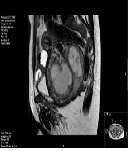

Degenerative Cervical Leiomyoma Resembling Malignant Leiomyosarcoma

Marieke C. Punt, Trudy G.N. Jonges, Manon N. Braat, Kartika Hapsari, Henk W.R. Schreuder*